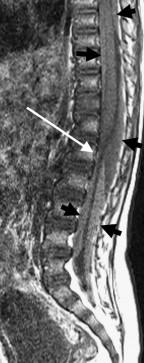

NAT: Spine MRI Cervical or Total, without contrast ½ to 2/3 of AHT have unsuspected spinal injury only .3-2.7% have bony abnormality on C spine

Brain swelling and herniation

Cord edema/ischemia Kadom et al, 2014, >75%

“Soft tissue or ligamentous injury” in the Cervical Spine

 Posterior soft tissue edema 50%

 Interspinous ligamentous edema/injury

 In cervical region, as high as 71% <1 year of age

Chaudhary, Kadom, Rabbitt 2019 Colombari, 2021

Spinal Injury patterns in AHT: SDH, compression fxs

[Choudharyetal,2014][Colombarietal,2021]

Nuchal ligament tear

Interspinous edema

Prevertebral fluid

Anterior vertebral body fracture T12 75% spine MRI: Extensive subdural/epidural hemorrhage, thecal sac tapering

Look for crowding and anterior displacement of the nerve roots